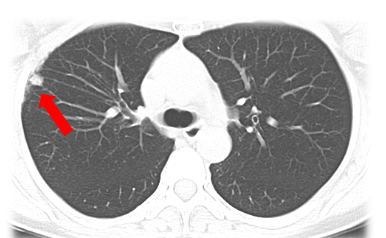

Z先生,28歲,不吸煙,無(wú)家族史、無(wú)高危環(huán)境及職業(yè)接觸史及慢性肺部疾病史,2022年體檢發(fā)現(xiàn)左肺小結(jié)節(jié),邊緣規(guī)則,大小約5mm, 醫(yī)生建議他做年度CT檢查。2023年體檢發(fā)現(xiàn)左肺結(jié)節(jié)部分吸收,大小為3mm。

![]()

肺小結(jié)節(jié)(直徑5-10mm)